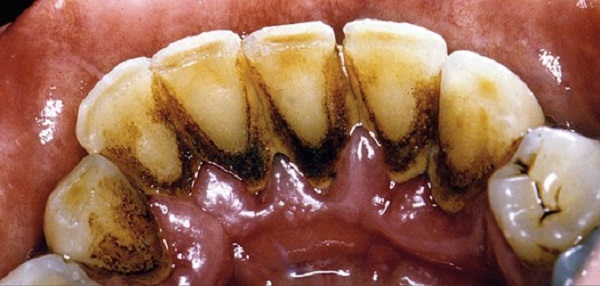

🔴 Cao răng màu đỏ (hoặc nâu đỏ): Đây chính là cao răng huyết thanh và thường xuất hiện ở bên dưới nướu. Trên thực tế, bạn đầu chúng chỉ là cao răng có màu vàng bình thường nhưng không được xử lý kịp thời nên gây ra các bệnh về nướu.

Khi nướu bị bệnh, mô mềm này sẽ rất dễ bị tổn thương, chảy máu hoặc chảy mủ. Máu khi ngấm vào cao răng sẽ biến chúng thành màu đỏ hoặc nâu đỏ.

➤ Khi cao răng bình thường trở thành cao răng huyết thanh (màu đỏ), sức “công phá” của chúng sẽ lớn hơn rất nhiều. Lúc này, bạn sẽ phải đối mặt với các nguy cơ bệnh lý răng miệng nguy hiểm hơn rất nhiều lần như viêm nướu răng, viêm nha chu, tụt nướu chân răng, viêm tủy răng, tiêu xương răng…